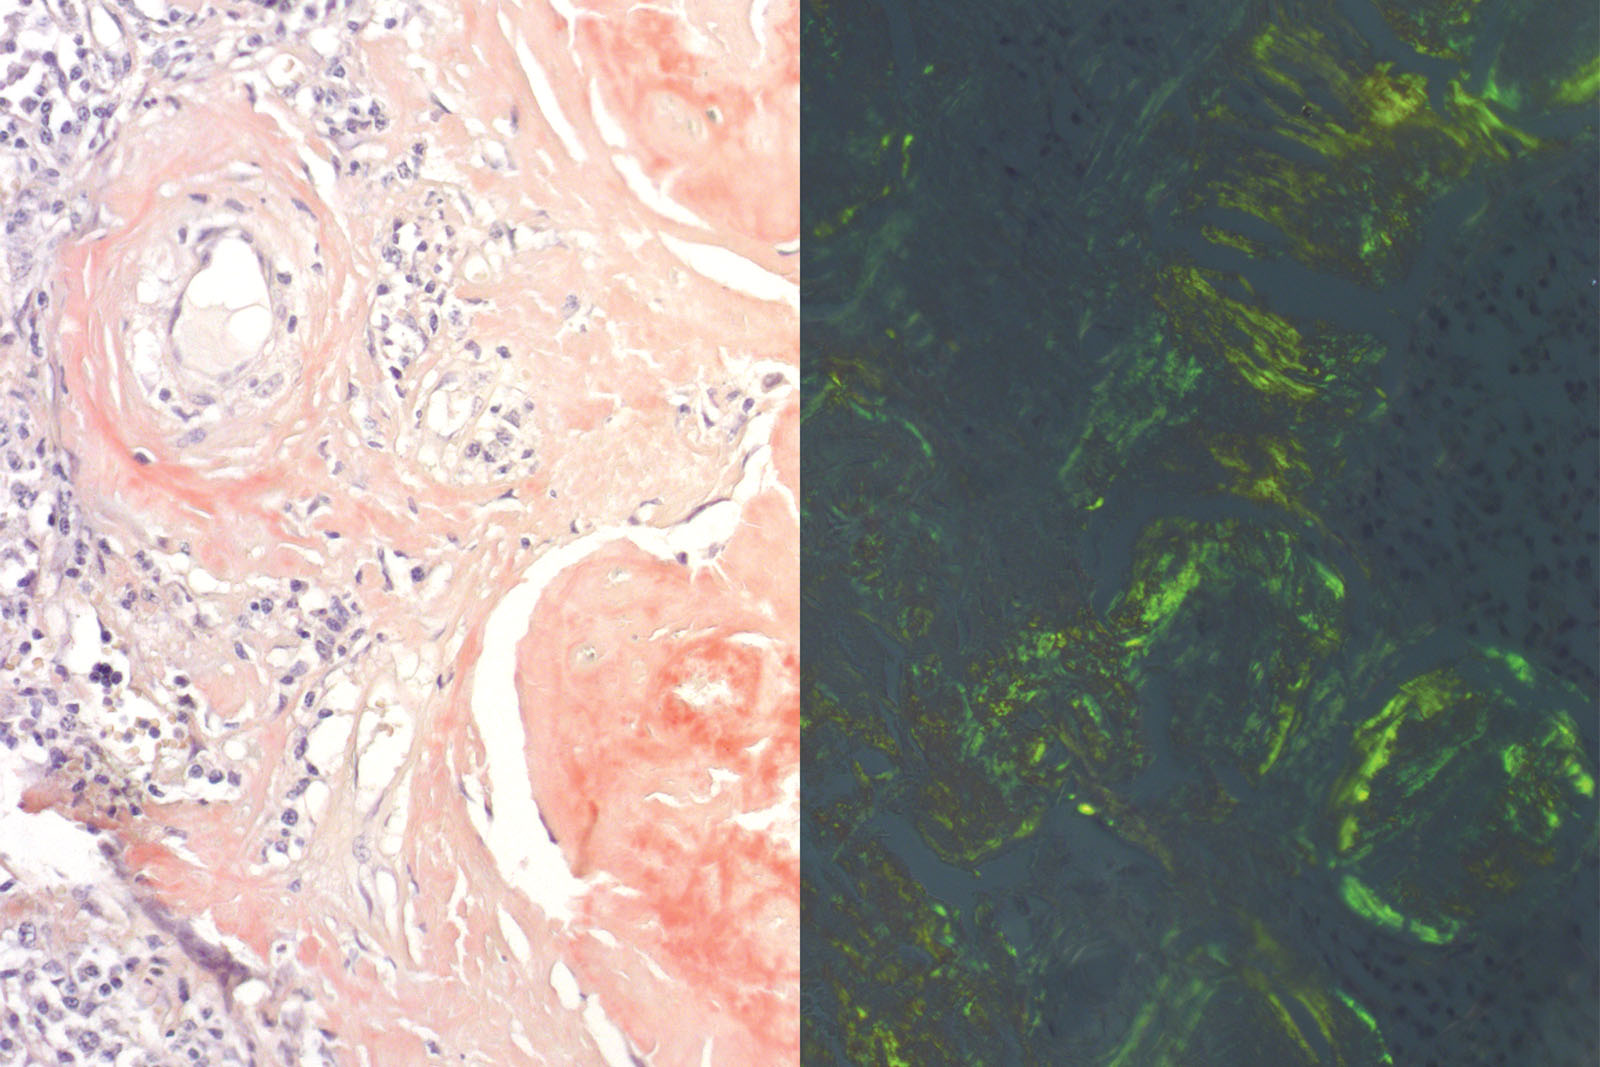

Congo Red Puchtler kit is used for staining amyloids (amorphous clusters) in histology sections. Despite their variable protein composition, amyloid deposits are linked by fibril beta-sheets formation. Congo Red dye binds to fibrils and form a regular pattern of dye molecules during the process. The structural regularity of the dye under polarized light demonstrates double refraction of light by displaying green coloration. High pH level and ionic strength of solutions according to Puchtler achieve higher dye specificity to amyloid.